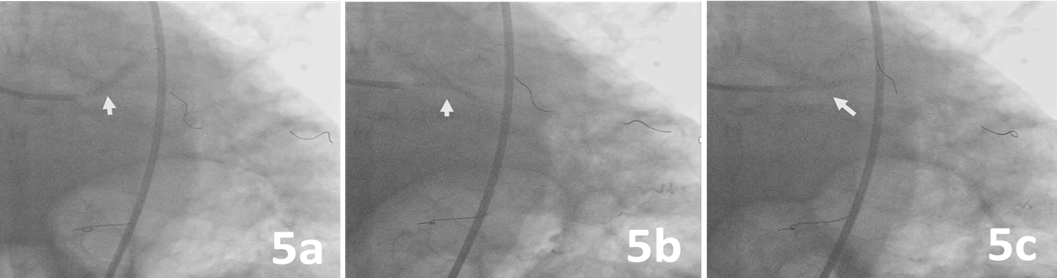

Predilatation was made from the LAD, ramus, and LCx to the left main artery with 3 Ryurei balloons (Terumo) at 8 atm (3.5 x 20 mm, 2.5 x 20 mm, and 2.5 x 15 mm, respectively) (Figure 5). A 3.0 x 32-mm synergy stent was deployed from the middle to the proximal segment of the LAD (Figure 6). Then, 3 stents were advanced and deployed simultaneously from the LAD, ramus, and LCx (Synergy 5.0 x 24 mm [Boston Scientific], Xience Sierra 3.0 x 33 mm [Abbott], and Synergy 3.5 x 16 mm, respectively) (Figure 7). Simultaneous triple-balloon (kissing) inflation at 12 atm was performed with three 2.0 x 15-mm Ryurei balloons (Figure 8); the 3 balloons were simultaneously inflated 3 times.